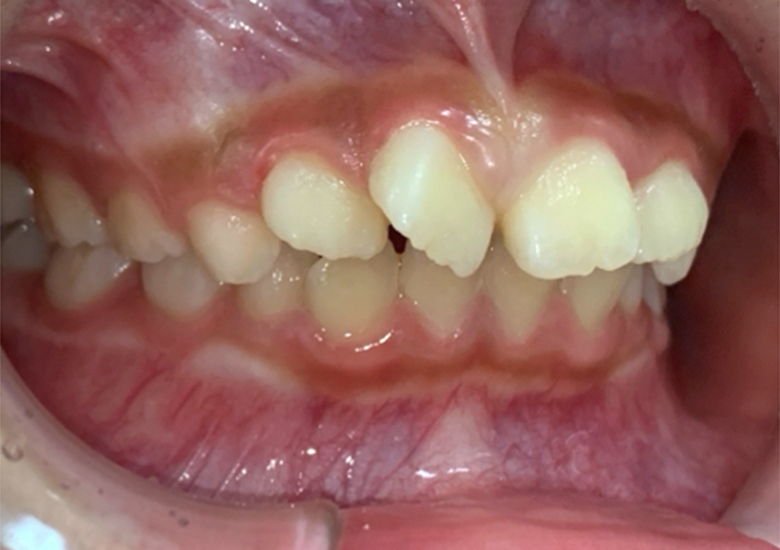

治療後

叢生/アクティビティ+インビザライン矯正 |

1.5年/18回 |

50万円(マイオブレイス+インビザライン)+アクティビティ 月一5500円 |